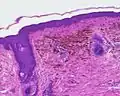

A blue nevus is a type of coloured mole, typically a single well-defined blue-black bump.[1][2]

The blue colour is caused by the pigment being deep in the skin.[4]